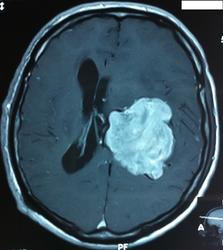

Начало вот здесь http://www.radiomed.ru/cases/kt-gms-obemnoe-obrazovanie-levoi-gemisfery-bolshogo-mozga-vnutrizheludochkovaya-meningioma. Пациент оперирован (меня сначала дезинформировали по поводу операции), перед операцией состояние ухудшилось, возникла правосторонняя гемиплегия, которая осталась и после декомпрессии. МРТ, КТ снимки и выписку предоставила супруга пациента, снимал на iphone, простите за качество, дисков с исследованиями не записывали. Надеюсь вопрос по данному случаю исчерпан.

Вот "цветочки":

T1+C

Т2

FLAIR

КТ контроль после операции.

Изначально по КТ я так предпологал, а теперь на 100% уверен, разве МРТ это не показало? Гистологически - менингиома, опухоль мозговой оболочки. Покажите, пожалуйста, образование где-нибудь прилежит к костям, где есть мозговая оболочка? Я не вижу, зато отчетливо вижу в левом боковом желудочке из оболочек сосудистого сплетения. Что вас еще смущает? По-моему, предостаточно фактов, чтобы развеять все сомнения.

Мне видится так. Иначе в данной локализации просто неоткуда расти оболочечной опухоли. На контрольной КТ, после декомпрессии, когда срединные структуры стали действительно срединны, правое обызвествленное сосудистое сплетение видно отчетливо, а левое, где оно? Ведь если бы образование компремировало, то после операции, когда часть мозга пролабировало в трепанационное отверстие мы бы увидели и левое сосудистое сплетение, но оно интимно связано с образованием и даже "потянулось" за ним в сторону декомпрессионного отверстия, потому что это и есть "росток" откуда выросла опухоль.